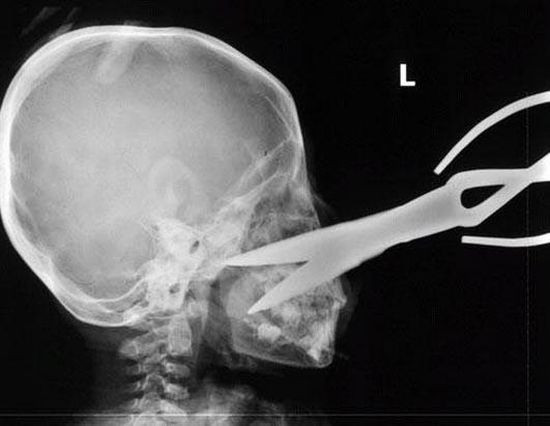

Radiografii terifiante: foarfece in cap, cuie in gat si furculite in mana

Surublenite infite in cap, plamani "dotati" cu cuie sau laringe "presarat" cu foarfece. Sunt numai cateva dintre cele mai ingrozitoare radiografii cu care s-au confruntat medicii de-a lungul timpului.

Iata mai jos o serie cu unele dintre cele mai "spectaculoase" radiografii.